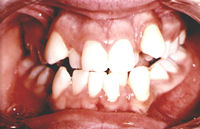

If your child develops an "open

bite", or you are otherwise concerned about the development

of your child's teeth, no matter what the age, contact us right

away for a consultation with Dr. Prather.